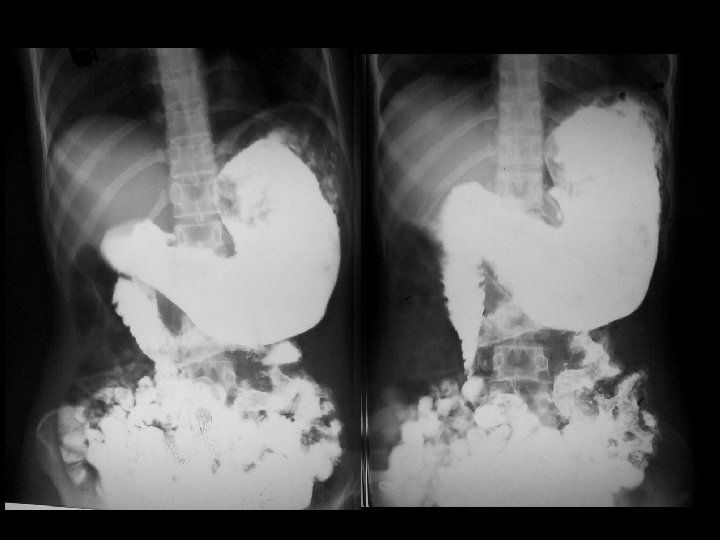

Barium meal showing a large, mottled, filling defect in the stomach extending into the duodenal bulb, & part of jejunum without any obstruction to the barium flow into the gut

• Filling up the stomach with barium demonstrates a mobile intraluminal filling defect of variable size, which may show extension into the duodenum. • The positive density of the mass due to residual contrast medium may be seen on delayed films. • With a small amount of barium the hair-ball gets coated and becomes visible. • The study should be continued till the contrast reaches the ileo-cecal region to look for any extension, dislodging or synchronism of the gastric bezoar.